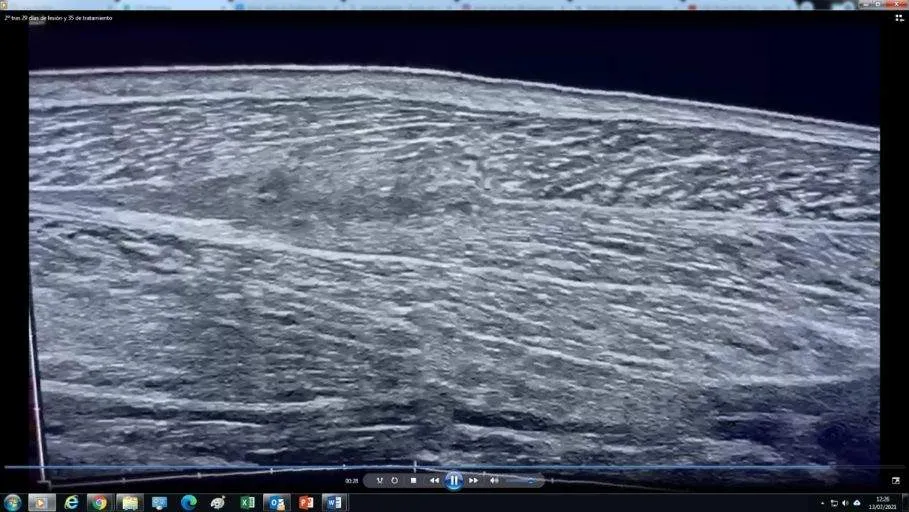

A esta otra Ecografía tomada a los 37 días de la lesión y 35 días de tratamiento (5 de julio) hay un gran trabajo realizado detrás.

“Cerramos herida de 3cm en 14 días y todo ha salido genial. Ahora queda el trabajo diario de maduración” nos comenta Bela muy satisfecho con la evolución de la lesión.